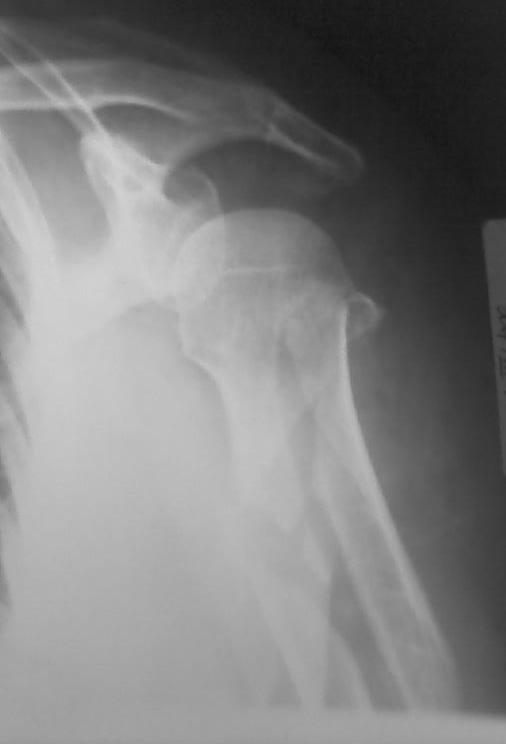

Высылаю рентгенограммы больной до операции и в гипсовой лонгете. Сейчас больную вообщем-то особо ничего не беспокоит, незначительная болезненность в области перелома при движениях плечом, первые два дня была отечность кисти, которая сейчас исчезла, объем движений в локтевом суставе постепенно увеличивается, отведение плеча пока небольшое. Дистальное блокирование выполнено одним винтом в передне-заднем направлении (через бицепс. Да, клинок мы конечно же заблокировали концевым колпачком. Нас тоже беспокоит возможность развития импиджмент синдрома, надеемся на то, что больная разработает движения в плечевом суставе.